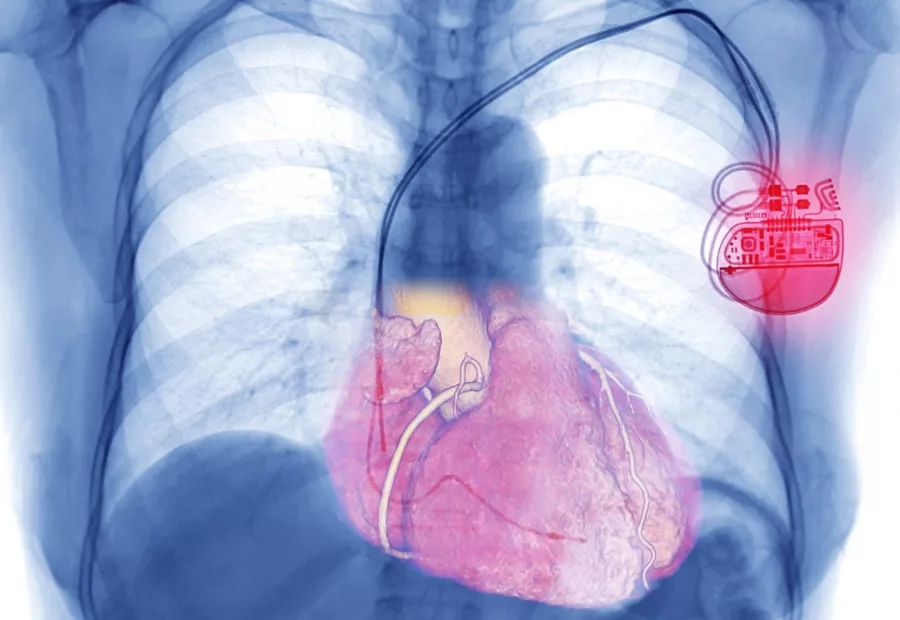

Moderne Herzschrittmacher bestehen aus einem Schrittmacheraggregat und ein bis drei hauchfeinen Sonden. Das Aggregat ist gerade einmal so groß wie zwei aufeinander liegende Zwei-Euro-Münzen und beinhaltet die nötige Technik, um das Herz mit gezielten Stromimpulsen so zu stimulieren, dass es schnell genug schlägt. Diese Impulse gelangen über die Sonden – dünne, kunststoffummantelte Kabel mit Elektroden an der Spitze – bis zum Herzmuskel. Dort geben die Elektroden kurze Stromimpulse, die eine Kontraktion des Herzens auslösen und ihm den Takt vorgeben. Angetrieben wird der Schrittmacher mit einer Lithiumbatterie, die mindestens sieben bis zehn Jahre hält.

An welchen Stellen und mit wie vielen Sonden ein Herz stimuliert werden muss, hängt von der Ursache der Herzrhythmusstörungen ab. Der Herzmuskel besteht aus dem rechten und dem linken Vorhof sowie der rechten und der linken Herzkammer. Normalerweise pumpt das Herz Blut durch den Körper, indem sich zunächst die Vorhöfe und anschließend die Herzkammern synchronisiert zusammenziehen. Die Impulse für die Vorhöfe stammen vom sogenannten Sinusknoten, die für die Herzkammern vom AV-Knoten. Die Probleme liegen in der Regel also bei einem von beiden.

Bei einer Erkrankung des Sinusknotens kommt meist ein sogenannter Einkammer-Schrittmacher zum Einsatz, der entweder den rechten Vorhof oder die rechte Herzkammer mit einer einzelnen Sonde stimuliert. Ein Zweikammer-Schrittmacher besteht aus zwei Sonden, sie sowohl den rechten Vorhof als auch die rechte Kammer stimulieren. Sie kommen bei Problemen mit dem AV-Knoten in Frage. Die seltenste Variante sind Dreikammer-Schrittmacher, bei denen eine dritte Elektrode bis in die linke Herzkammer führt. Sie bieten sich etwa dann an, wenn der Herzmuskel stark geschwächt ist und sich die Herzkammern nicht mehr synchronisiert zusammenziehen können.

Röntgenbild eines Brustkorbs mit Herzschrittmacher

Zweikammerschrittmacher mit Elektroden zur rechten Vorkammer und zur rechten Hauptkammer des Herzes.